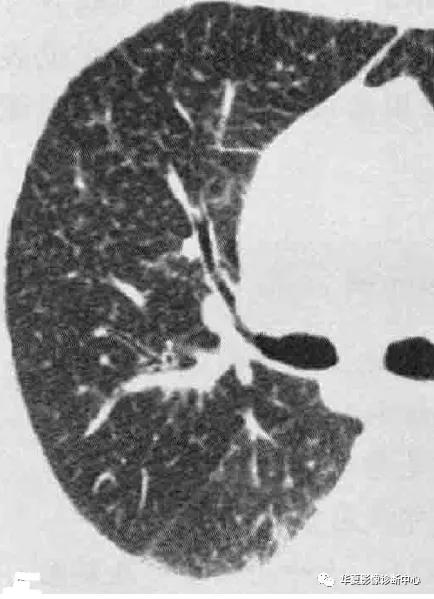

影像学表现:大多数转移性钙化患者X线表现正常,如果异常,表现包括大量直径3-10mm松散的、边界不清的结节灶,类似空腔结节或肺实质病变的斑片状病灶,主要累及上肺,钙化在X线不大明显。CT典型表现为松散的、边界不清的、直径3-10mm结节,位于小叶中心且上叶分布最多,边界可很清楚,结节钙化可是点状、分散的,或偶尔环形,钙化血管典型的可见于胸大肌和胸小肌之间,还可能出现广泛磨玻璃、斑片状实变及肺动脉和左心房壁的钙化。